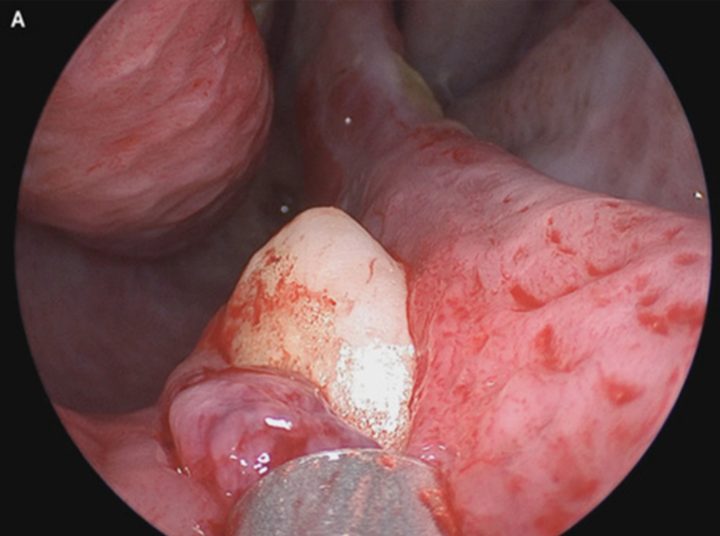

取出卡入鼻腔的异物